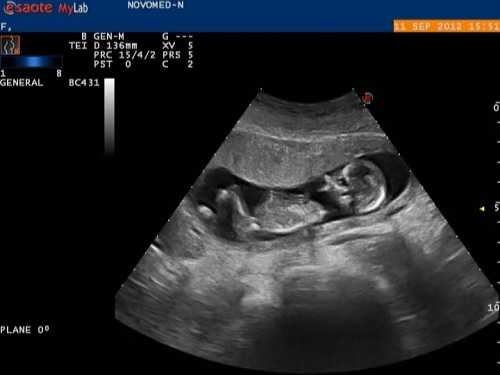

Генетический сбой в период закладки челюстно-лицевой системы приводит к развитию дефектов — незаращению верхней губы и неба. Распознать наличие волчьей пасти у плода возможно по УЗИ лишь на поздних сроках беременности. Дети с заячьей губой и волчьей пастью болезненны, т. к. вдыхаемый ими воздух не согревается и не увлажняется, что приводит к развитию воспалительных процессов дыхательных путей и внутреннего уха. У таких пациентов отмечаются изменения челюстно-лицевого скелета, зубочелюстного ряда, слухового аппарата. Незаращение нёба и верхней губы может встречаться изолированно или сочетаться вместе и с другой челюстной патологией.

Ультразвуковое исследование на четырнадцатой-шестнадцатой неделе беременности способно предварительно диагностировать образовавшуюся волчью пасть у плода, но точно установить факт патологии и оценить объем поражения неба в полной мере можно только после появления малыша на свет.

Сбой в этом тонком и сложном механизме и приводит к развитию дефекта незаращенного неба и верхней губы. К сожалению, этот дефект можно распознать при ультразвуковом обследовании, но только на поздних сроках беременности. Однако, эта информация очень важна как для самой женщины, так и врачей-акушеров.

Диагностика

Выявить дефект расщепления неба можно при помощи планового УЗИ-скрининга плода уже примерно на 15-й неделе беременности. Но объем и форму поражения можно рассмотреть только после рождения малыша. Если при ультразвуковом исследовании обнаружена волчья пасть у будущего ребенка, то обязательно требуются дополнительные методы исследования. Это отклонение чревато патологиями развития черепной коробки, нарушениями слуха, ухудшением дыхания и обоняния. Диагноз «волчья пасть» устанавливается сразу же после рождения ребенка. При этом степень дефекта и его тип определяются путем осмотра зева малыша.